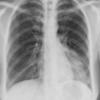

Case 3 RM & UL pneum PA

Date: 07/04/2004

Views: 5448